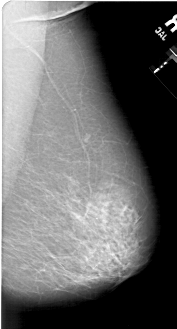

A_1594_1.LEFT_MLO

LEFT_MLO LINES 6871 PIXELS_PER_LINE 3316 BITS_PER_PIXEL 12 RESOLUTION 43.5 OVERLAY

FILE: A_1594_1.LEFT_MLO.OVERLAY

TOTAL_ABNORMALITIES 1

ABNORMALITY 1

LESION_TYPE MASS SHAPE OVAL MARGINS ILL_DEFINED

ASSESSMENT 4

SUBTLETY 5

PATHOLOGY MALIGNANT

TOTAL_OUTLINES 1

BOUNDARY